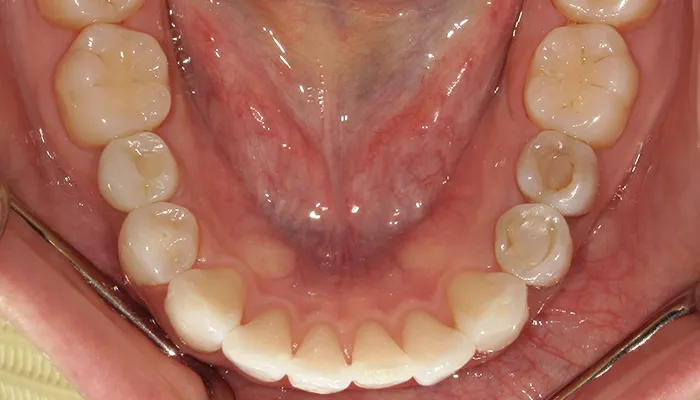

治療前

口腔内写真とレントゲン写真

右下5番は大きく崩壊しており、保存不可能な状態でした。

また、下顎前歯部を中心に叢生があり、歯列が不均一でした。咬合関係が不安定で、清掃性も低下していました。

全体的に歯の色もやや黄みを帯びており、患者様からも審美的な改善希望が強くありました。